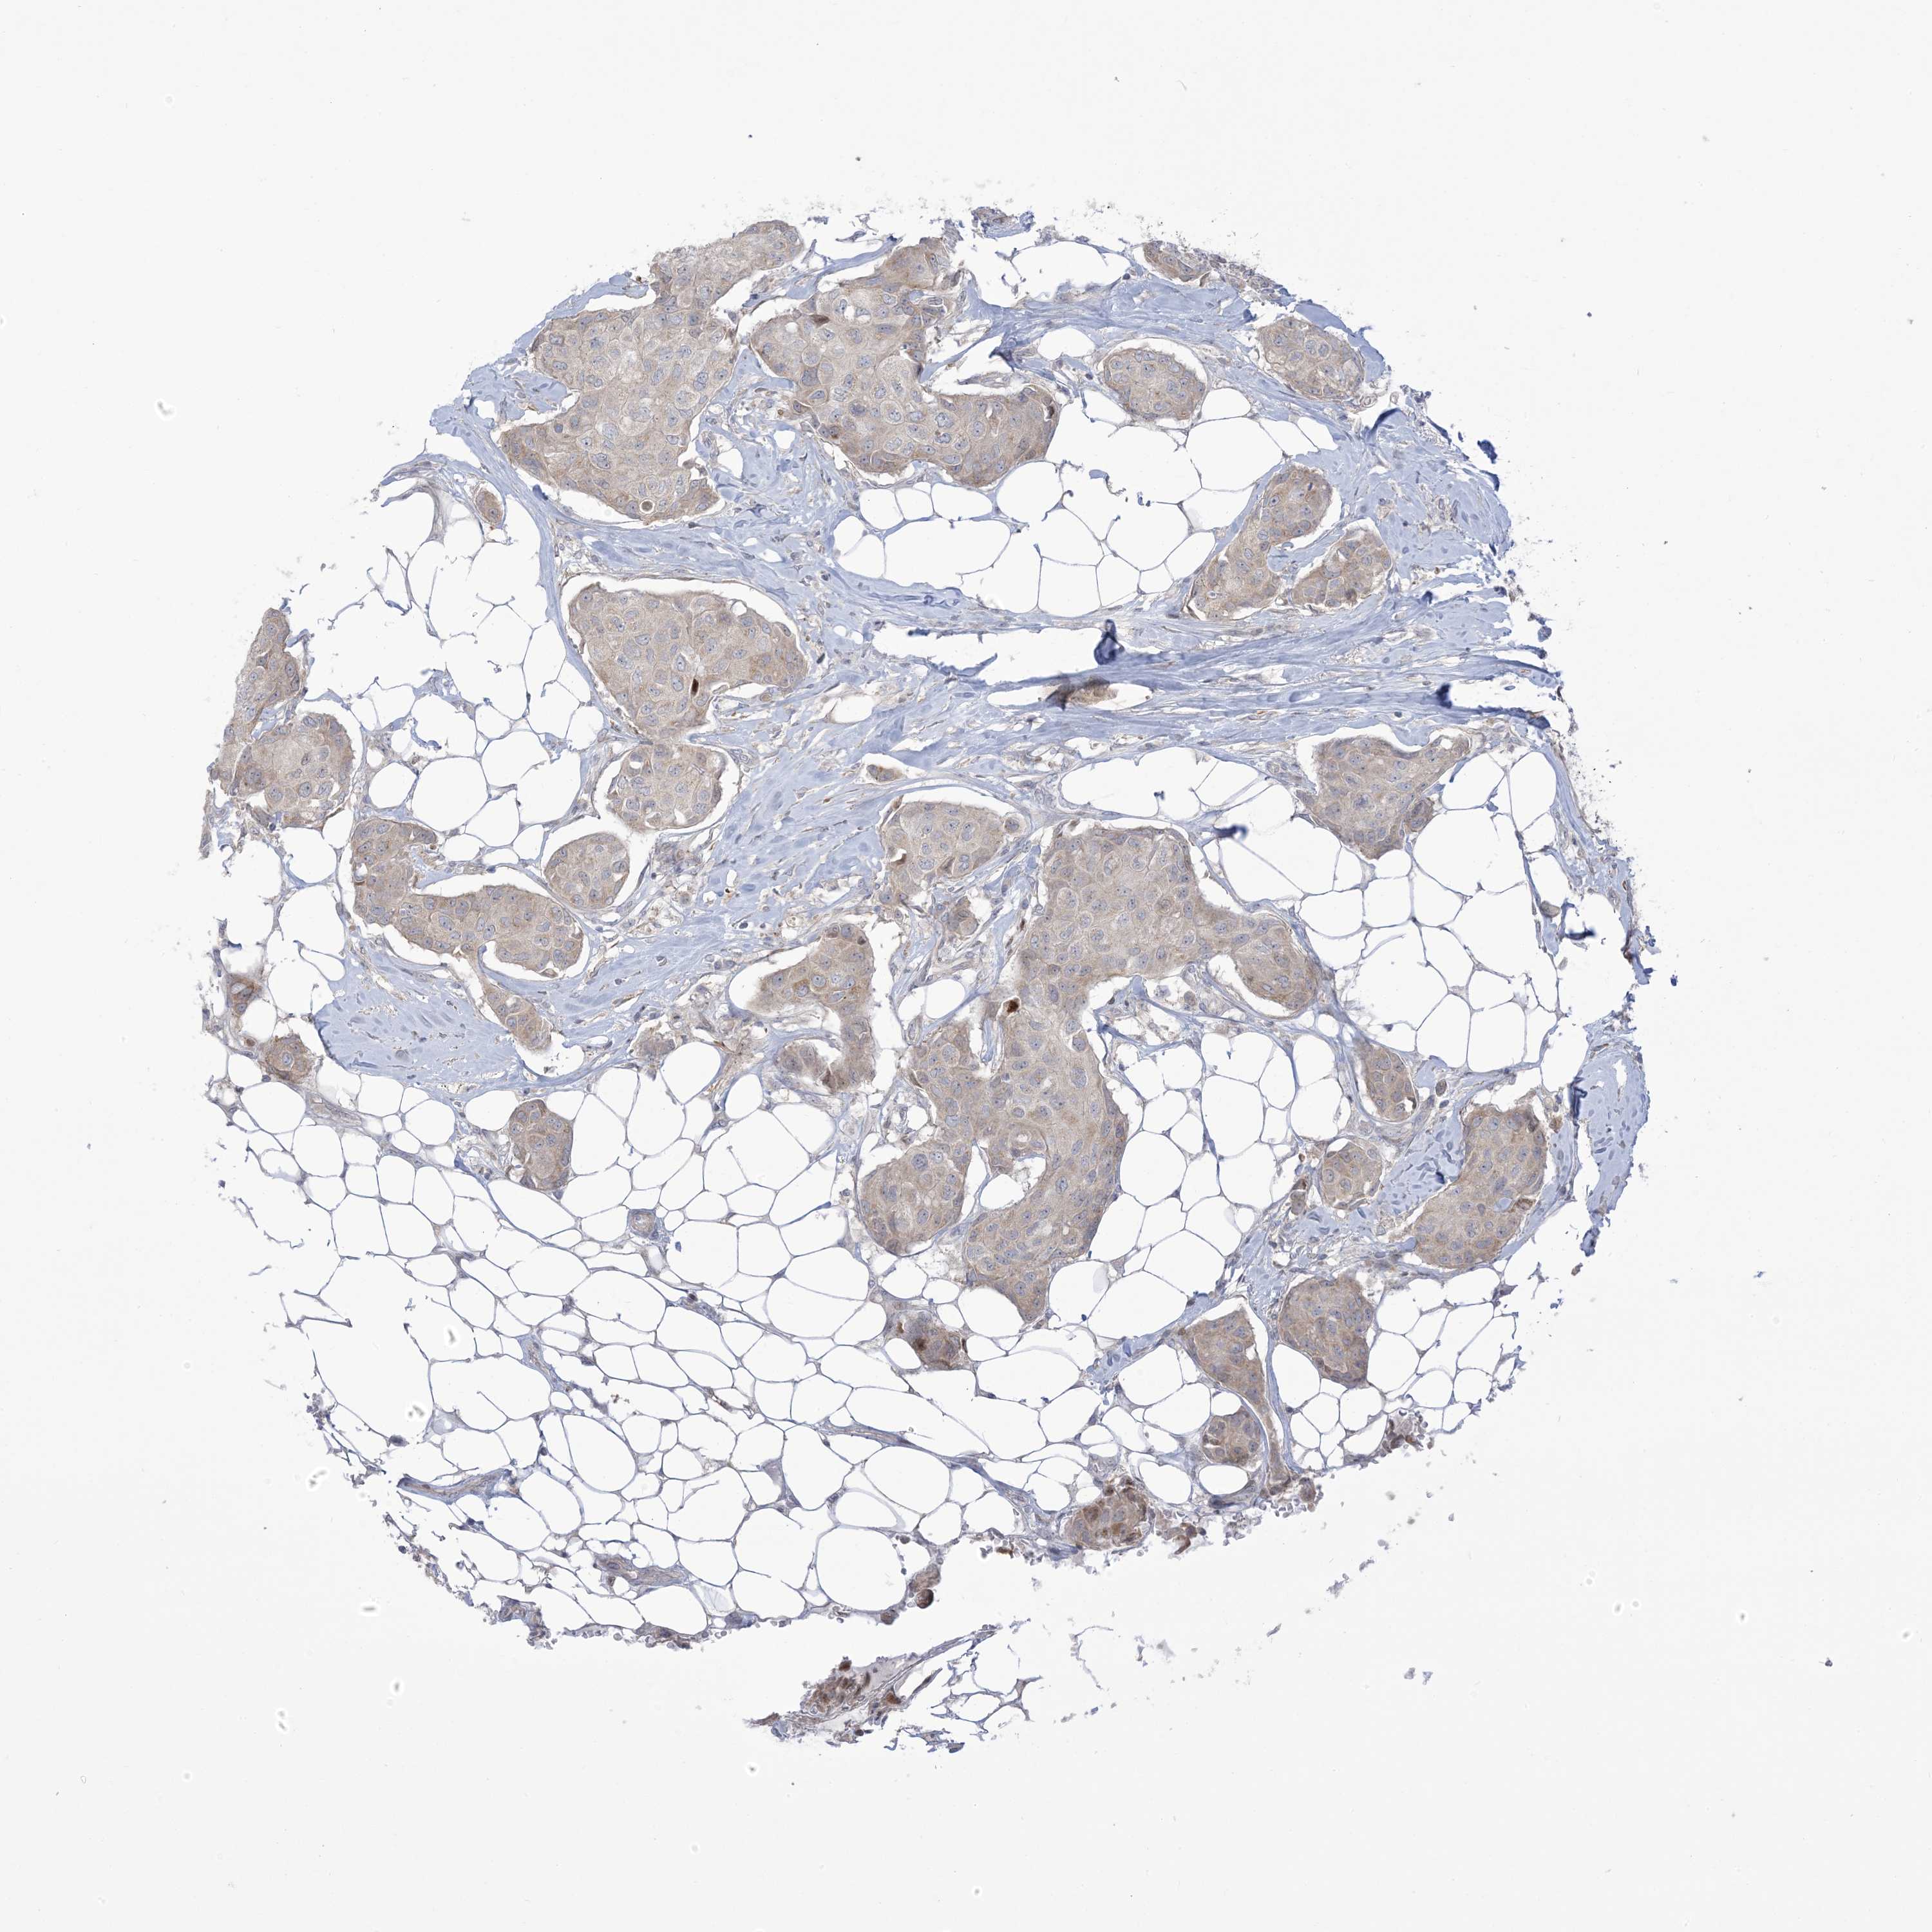

CANCER BREAST CANCER Show tissue menu

BRCA TCGA BRCA VALIDATION PROTEIN EXPRESSION